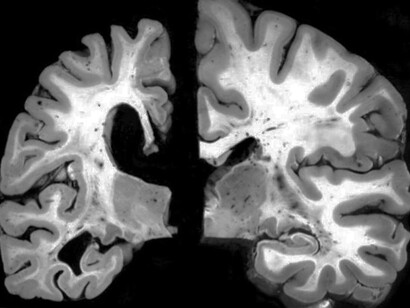

El mecanismo inicial de infección parece ser el reconocimiento y fusión por parte de la proteína S denominada espiga (spike) de la superficie del SARS-CoV-2 con el receptor para la enzima convertidora de angiotensina 2 (ACE2) en humanos; esta última expresada en el endotelio capilar del cerebro y multitud de órganos. En relación con esta información, recientemente se ha demostrado la presencia de SARS-CoV-2 en muestras de autopsias a nivel del SNC en los revestimientos endoteliales en las áreas adyacentes a las áreas necróticas en pacientes enfermos de COVID-19. Además, se ha aislado SARS-CoV-1 del tejido cerebral con edema neuronal y degeneración a partir de autopsias. Todo esto se ha llevado a cabo con métodos de inmunohistoquímica, hibridación in situ y confirmación microscópica electrónica de la infección viral de neuronas.